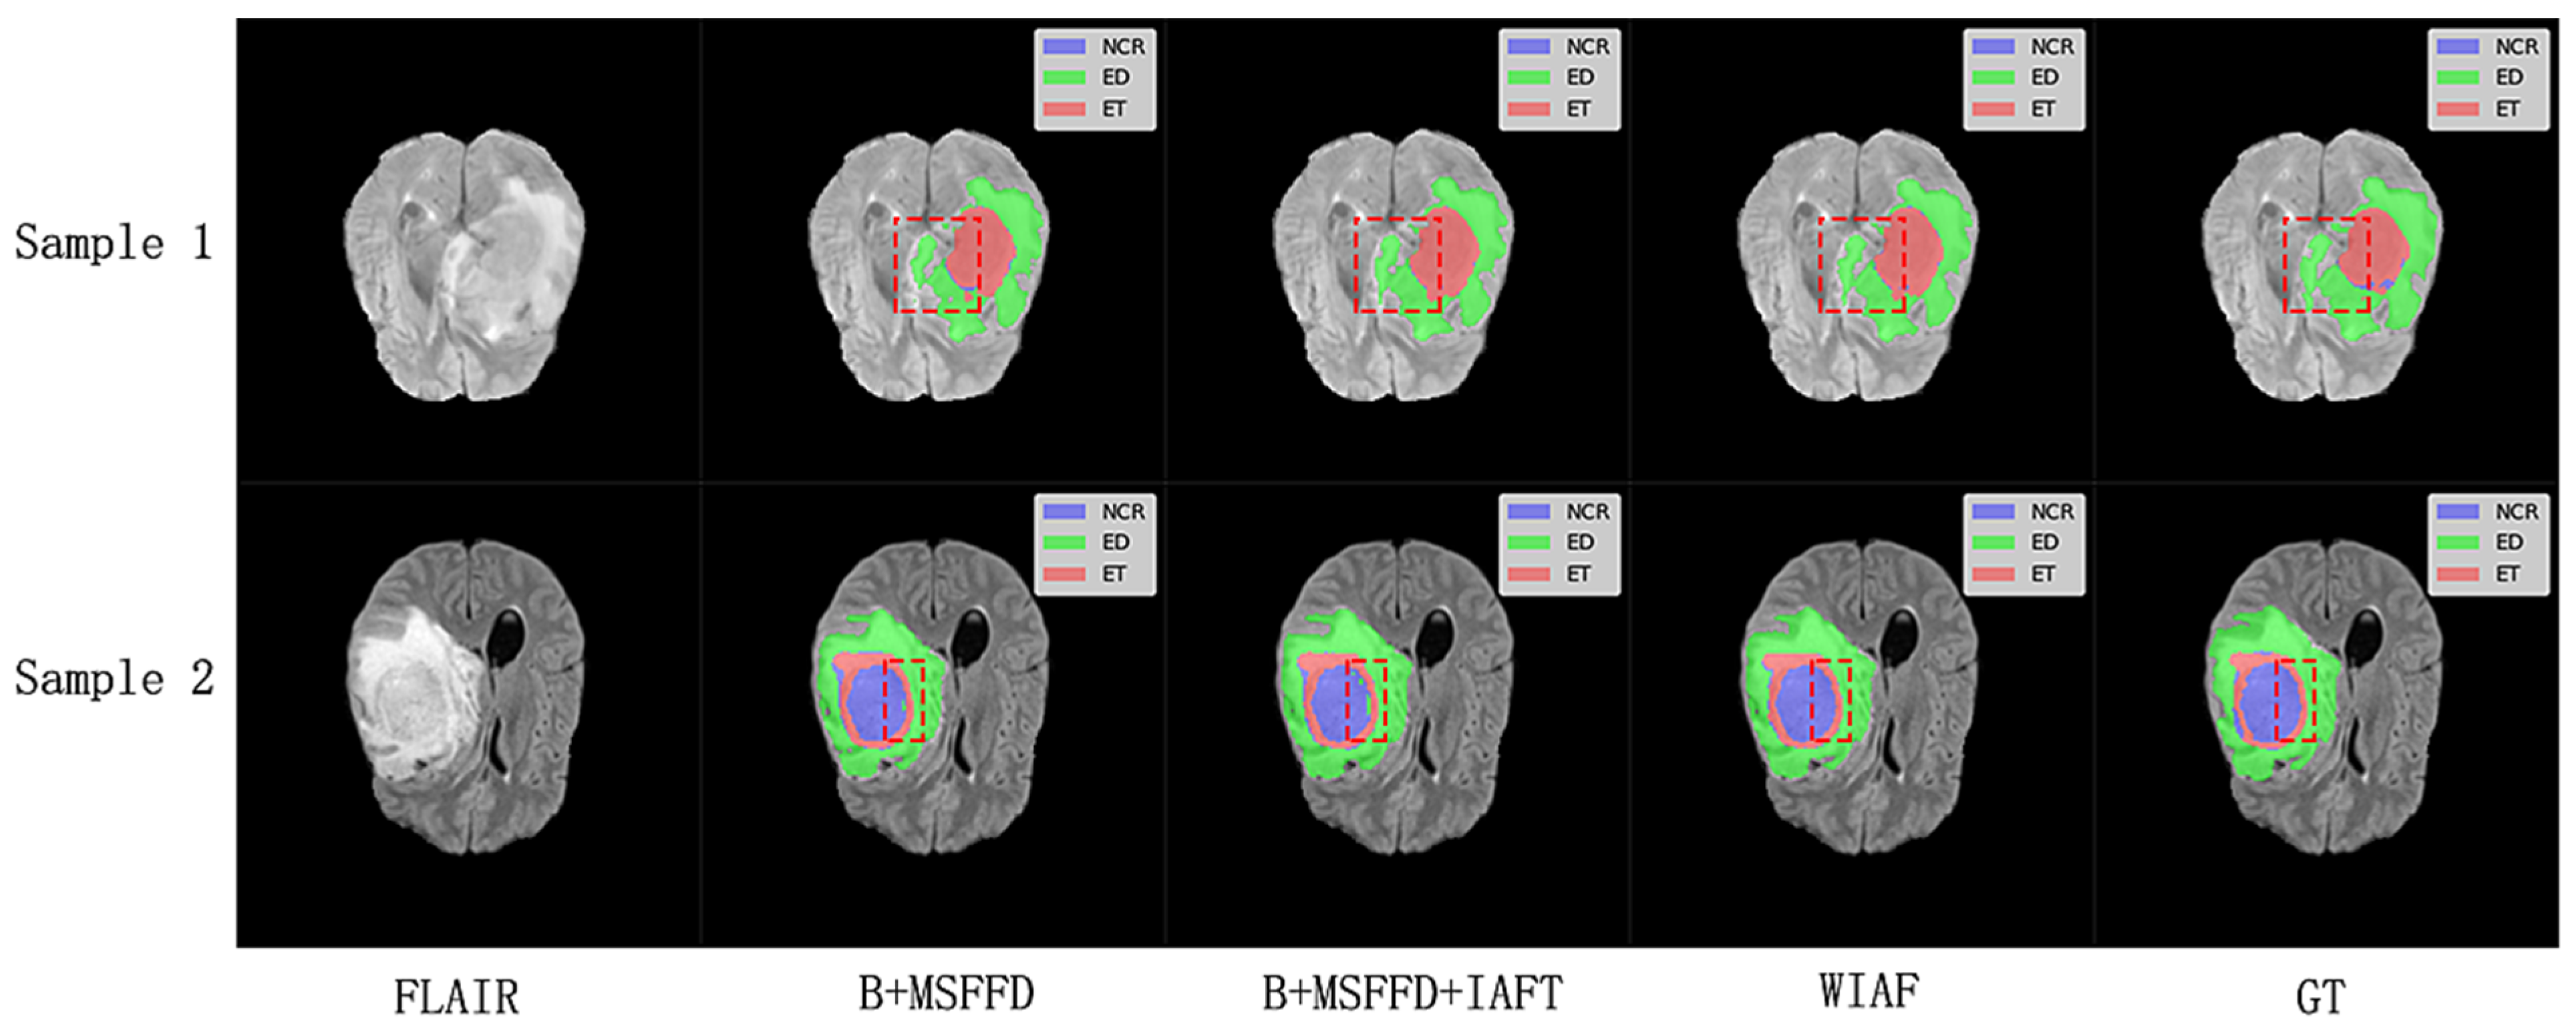

The visual results shown in Figure 9 further validate the quantitative findings of the ablation study. The model without IAFT and AWD-FD exhibits significant undersegmentation in the ED region compared to the ground truth labels, and the boundaries of the WT region are not defined with sufficient precision. After integrating the IAFT module, a significant improvement in tumor boundary segmentation was observed, highlighting the effectiveness of IAFT in modeling long-range dependencies and optimizing feature representations. Finally, the complete proposed model incorporating the AWD-FD module is the closest to the ground truth (GT). The AWD-FD module appears to further optimize segmentation by preserving finer details and improving contour accuracy, particularly in the ED region and at the interfaces between different tumor subregions. For example, the highlighted regions in Sample 2 indicate that the model successfully captured subtle infiltration patterns and reduced false positives within the tumor compared to the intermediate ablation stage. This qualitative evidence strongly supports the synergistic contribution of each proposed module toward achieving robust and accurate brain tumor segmentation.

Figure 9. Qualitative comparison of ablation study results on a representative axial slice from the BraTS2020 testing dataset. The red dashed boxes highlight the key differences between the model predictions at different stages and the ground truth labels.